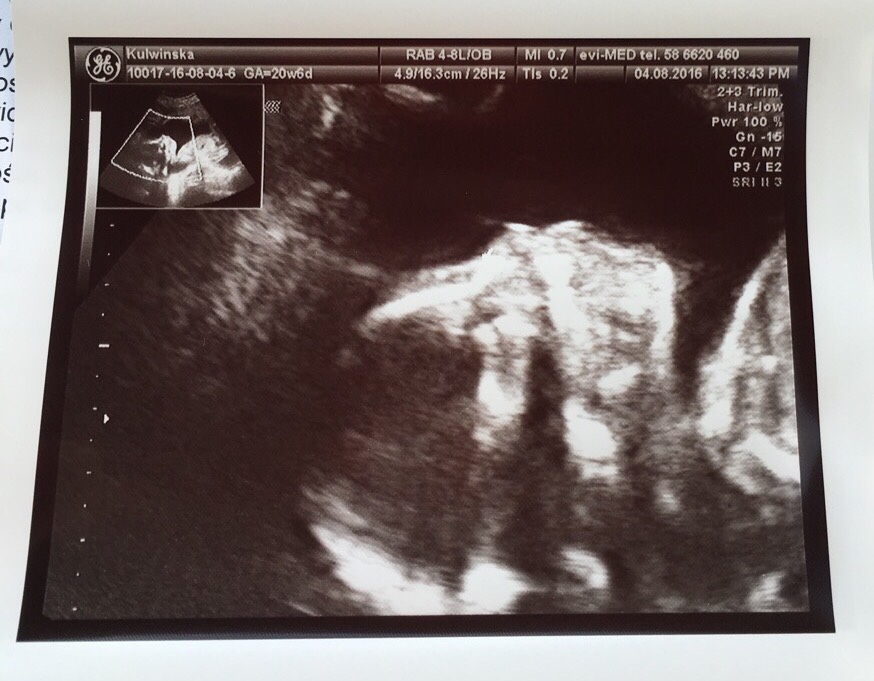

No i ja po juz...pół kilo zdrowego syna!!![emoji170][emoji170][emoji170][emoji7][emoji7][emoji7][emoji7]

Lekarz już zaznaczył, że łatwo nie bedzie, bo na bank rośnie pod 4 kg...![]()